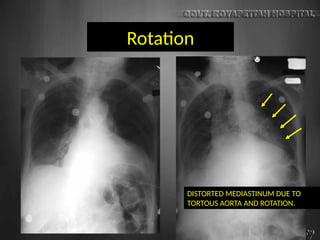

Rotation

DISTORTED MEDIASTINUM DUE TO

TORTOUS AORTA AND ROTATION.